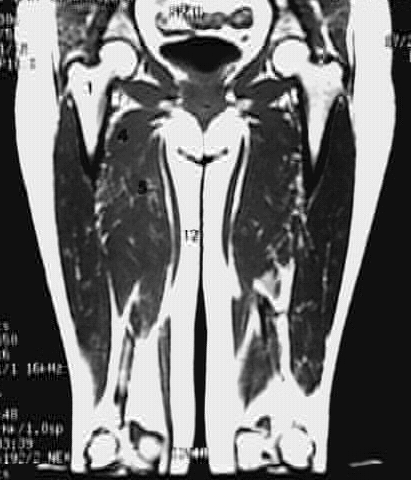

Lower Limbs: Thigh Coronal Zoom 2 of 3